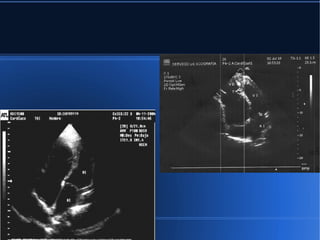

● Esta imagense designa habitualmente como la de "amputación del ápex ventricular". Se observa un aumento de la reflectancia de la superficie obliterativa. El movimiento apical del ventrículo izquierdo es centrípeto, es decir hacia el interior de la cavidad. El proceso de obliteración afecta a los tractos de entrada de uno o de ambos ventrículos, pero respeta el tracto de salida.

● El patrónintegrado por "pequeños ventrículos - grandes aurículas". La vista de cuatro cámaras constituye la mejor proyección para visualizar este patrón característico pero no específico de "pequeños ventrículos- grandes aurículas"